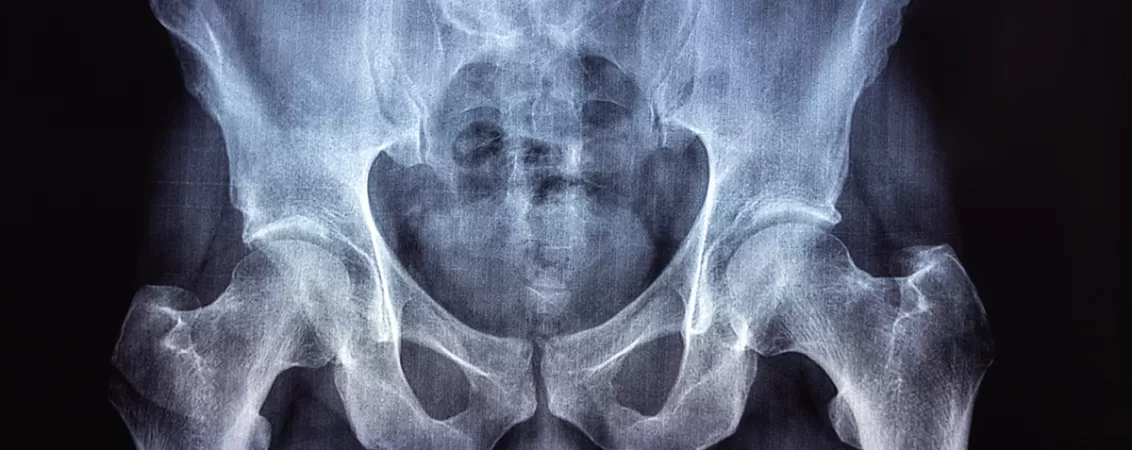

Un RMN de bazin osos este o investigație imagistică avansată, non-invazivă, care oferă imagini detaliate ale structurilor din regiunea bazinului.

Bazinul osos este o structură rigidă, în formă de inel, vitală pentru stabilitate și protecția organelor. În esență, este compus din două oase coxale mari în față (care includ oasele iliace, ischiatice și pubiene) și din sacru (osul sacrum) și coccis în spate. Toate acestea formează inelul pelvin, a cărui stabilitate excepțională este conferită de ligamente puternice. Acest inel se conectează prin patru articulații principale: două articulații sacroiliace, simfiza pubiană (în față) și articulația sacrococcigiană (la bază).

La RMN-ul de bazin osos, se pot vedea atât detalii osoase, cât și aspectul cartilajului articular, al ligamentelor, mușchilor sau vaselor de sânge din zonă, ceea ce permite depistarea unei game largi de afecțiuni.

RMN-ul examinează oasele pelvine, articulațiile majore, măduva osoasă, precum și țesuturile moi din jur, cum ar fi ligamentele, tendoanele și mușchii.